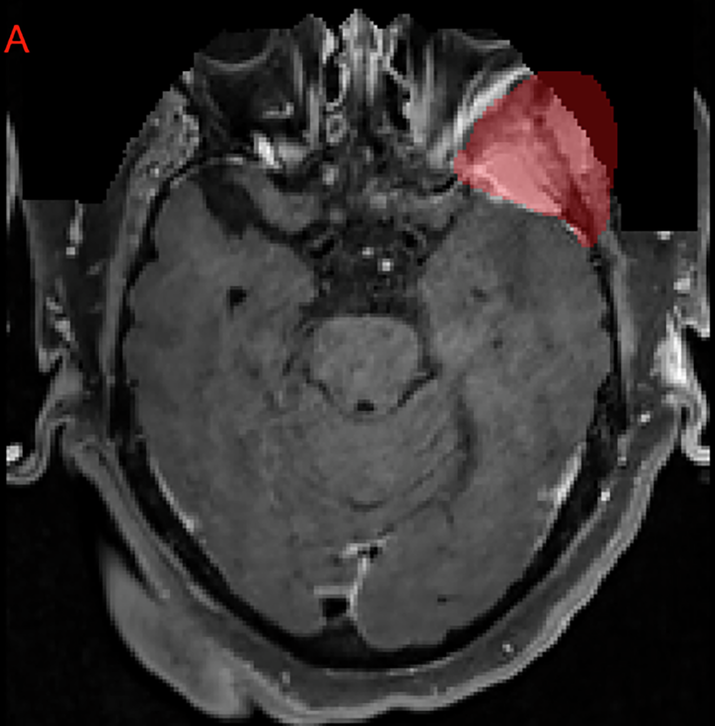

Fig. 6

From: The 2024 Brain Tumor Segmentation Challenge Meningioma Radiotherapy (BraTS-MEN-RT) dataset

Example of an axial MRI image-label pair slice where the treating institution’s meningioma GTV extended outside of the defaced image. Note that this left sphenoid meningioma involves the skull base and extents extracranially into the left masticator space. This case was ultimately excluded from the challenge dataset due to the excessive volume within the anonymized region that would have needed to be reintroduced.